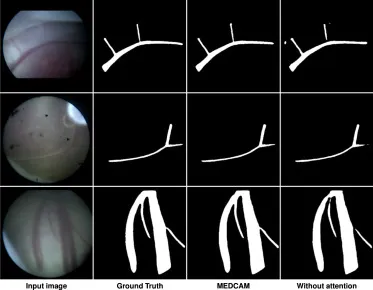

图10. MEDCAM模块对胎盘血管分割影响的定性比较。每行显示一个测试集示例。输入图像、真值、MEDCAM和无注意力模块的结果分别从左到右呈现。